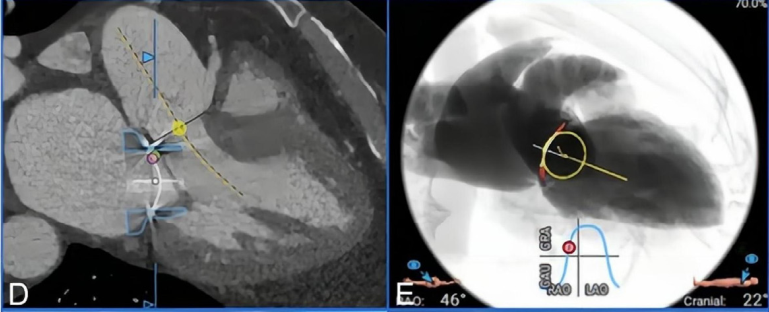

Professor Yang Jian’s team at Xijing Hospital conducted a detailed assessment of the patient’s transesophageal echocardiography (TEE) and CTA images, considering the patient’s significant symptoms and the extremely high risk of re-thoracotomy (STS score 11.192%; EuroSCORE II score 8.3%), ultimately deciding to perform TMViR (see Figure 1A–E).

Figure 1. (A-E) Preoperative imaging assessment.(A) Preoperative echocardiography indicated severe mitral regurgitation. (B–E) Preoperative CTA was used to assess the mitral valve annulus and left ventricular outflow tract structure. (B) The area of the mitral valve repair ring was 7.0 cm². (C, D) After simulating the implantation of the Mi-thos biological valve, the new left ventricular outflow tract area was 374.6 cm², with no obstruction observed. (E) The projection angle for valve implantation during surgery was RAO 46°, CAU 22°.